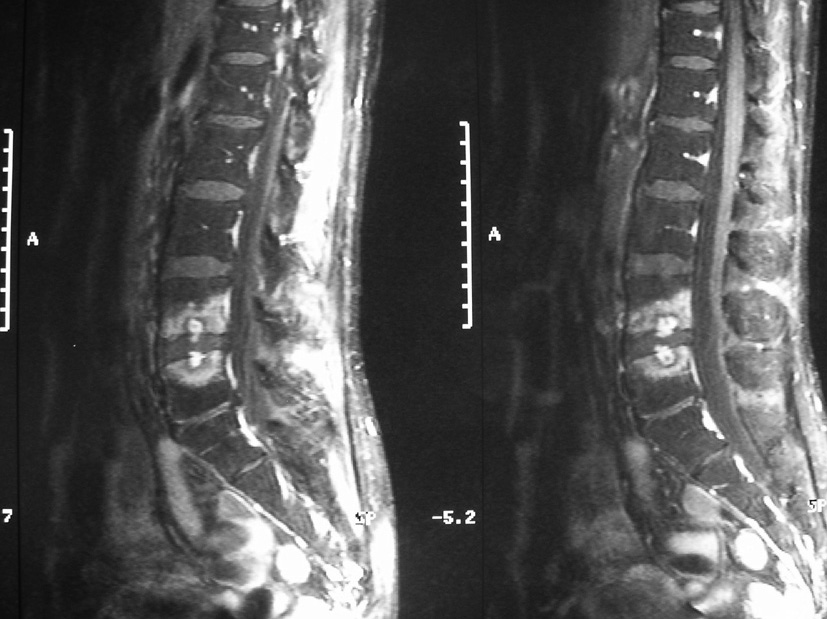

Quelques jours plus tard, malgré un traitement médical bien conduit, le patient bénéficie finalement d’une discectomie L4-L5 chirurgicale en urgence du fait d’un déficit avec un syndrome de la queue de cheval. Il est dans un premier temps amélioré, avec notamment régression de la radiculalgie. Cependant, deux semaines après la chirurgie, il présente une réaggravation de ses lombalgies. Ces dernières sont permanentes, insomniantes, non irradiées. Il existe une fièvre à 38-38,5 °C. La vitesse de sédimentation est de 45 mm à la première heure et la protéine C réactive à 120 mg/l. Une IRM est réalisée (T1 + gadolinium) (cliché ci-dessous).